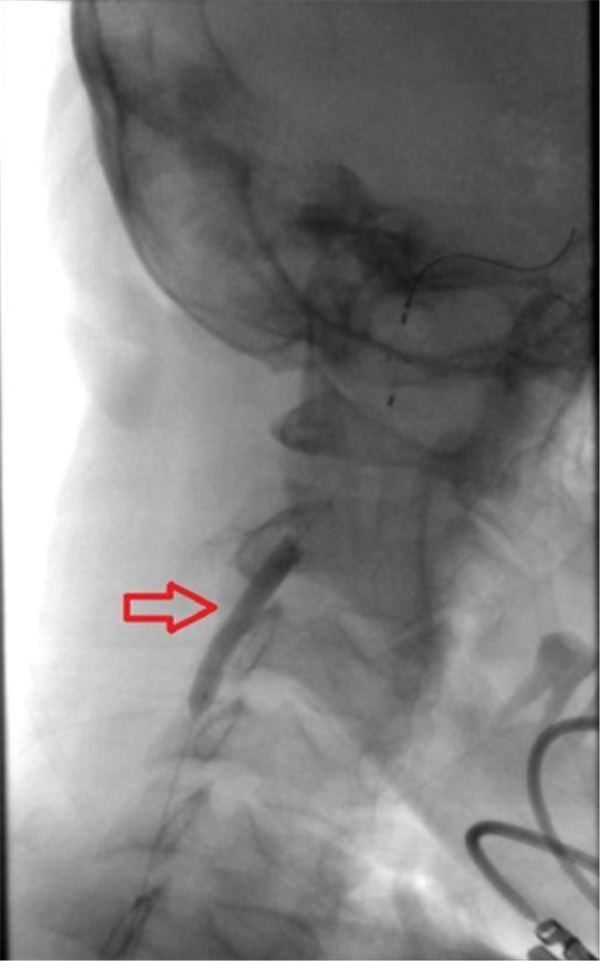

球囊完全扩张后,可见狭窄部位血流通畅(上图红色箭头所指)。

球囊完全扩张之后,动脉狭窄消失(上图红色箭头之间)。